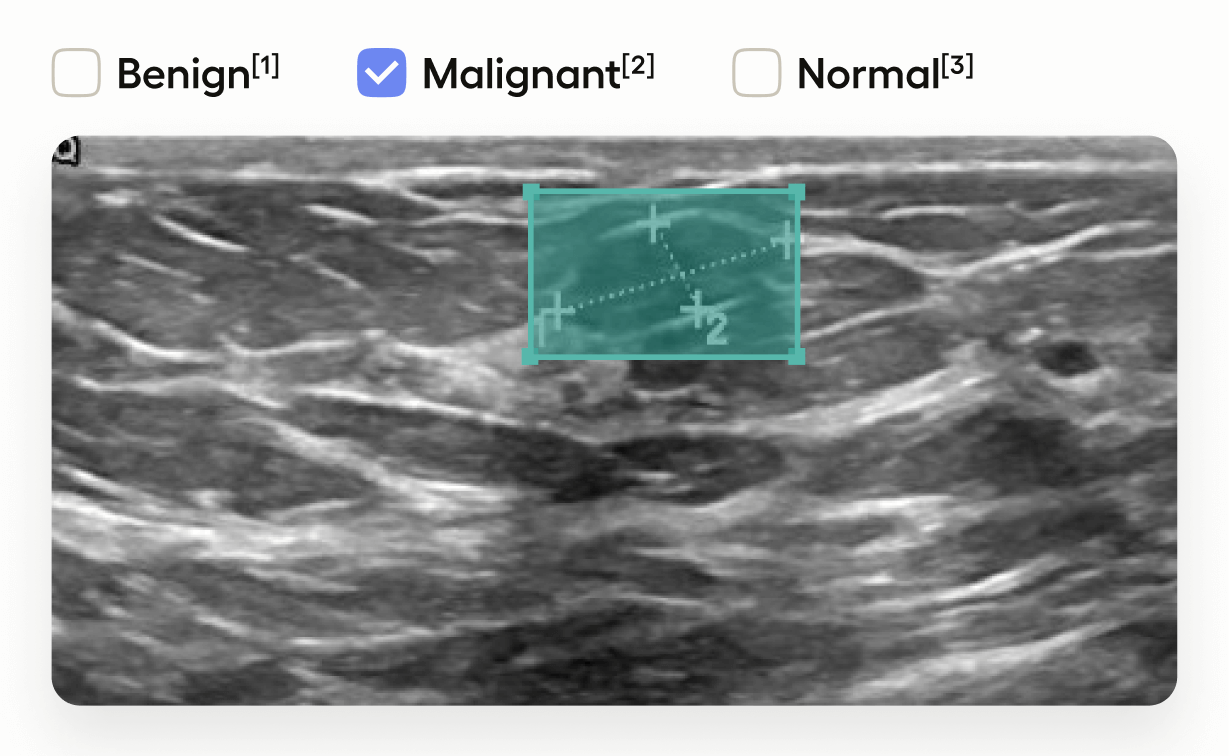

Medical Image Classification with Bounding Boxes

This template interface allows annotators to:

• Draw bounding boxes around areas identified as tumors in the image using the โ€œTumorโ€ label.

• Classify the entire image by selecting one of โ€œBenignโ€, โ€œMalignantโ€, or โ€œNormalโ€.

This setup is useful in medical imaging tasks where you need to localize tumors and also provide an overall assessment of the image.